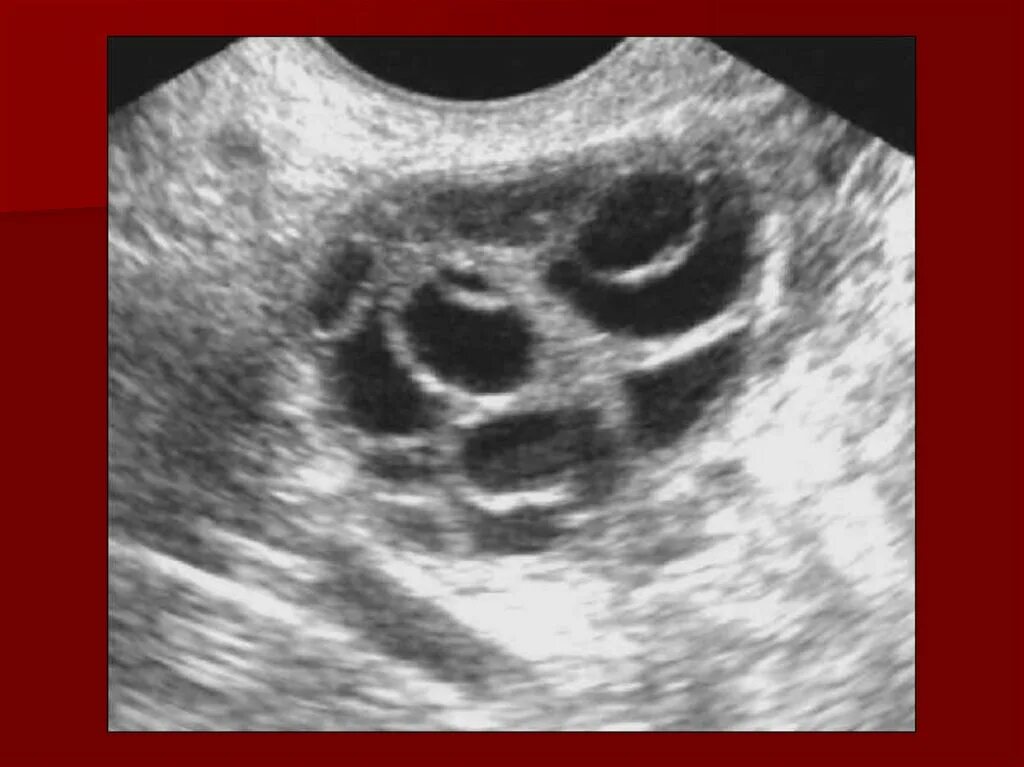

Узи овуляции как называется